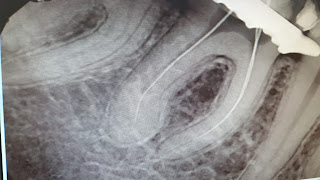

Y aqui el Dr. Jorge Llorente nos presenta este caso de un Radix entomolaris que acude a Mississippi por caries mesial muy invasiva. Se diagnostica, ayudado por la Dra. Marta Reviejo, profesora del Master, como una pulpitis irreversible a un paciente sin nada que reseñar de su historia medica. Y se realiza el tto. haciendo varias proyecciones y asi ver en todo momento las longitudes de todas los conductos. Lo difícil de estos casos, aparte por supuesto de diagnosticarlos al empezar con la rx de dco. es conseguir mesializar y distalizar a la hora de tomar las rx periapicales. Las longitudes fueron de 21mm los mesiales y el distal 22mm.

Se instrumentaron con limas manuales K hasta un ISO 20 y luego rotatorias con Protaper Next, hasta X3 en la distal y X2 en las mesiales, realizando un pre flaring con la SX de protaper universal.

La irrigación muy abundante con NaOCl 5,25% entre limas y EDTA para eliminar Smear Layer al pasar la ultima LAM.

La obturacion y sellado de conductos con gutapercha caliente, usando el Elements free y

con gutapercha Autofit de 06. Cemento AhPlus.

Aqui colgamos las Rx: